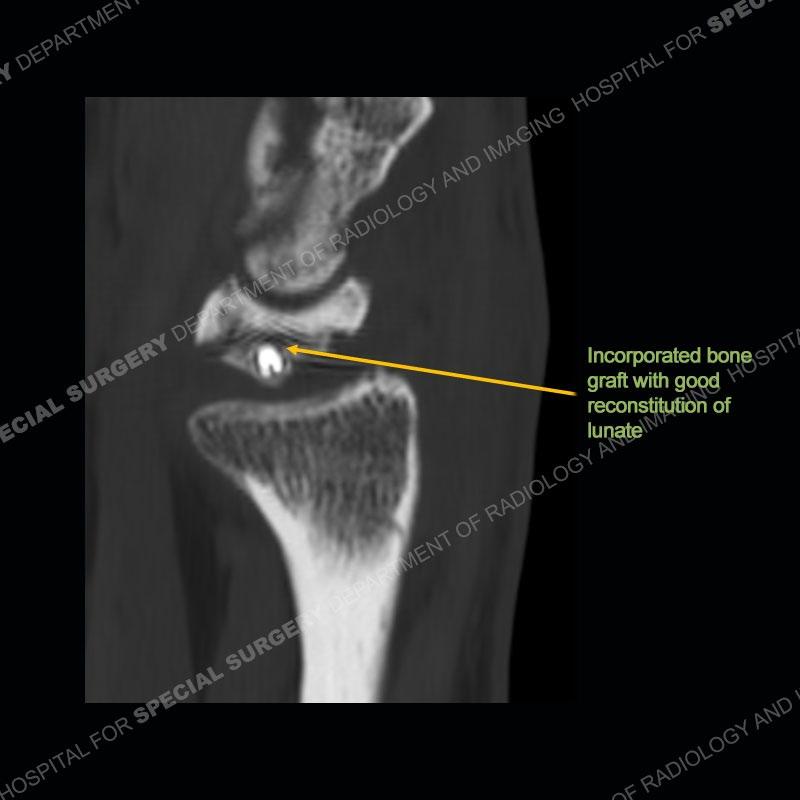

The treatment as the underlying cause of Kienbock’s remains somewhat elusive. Prior to collapse, osteotomies to decrease load or shearing forces to the lunate may be helpful. Once collapse and arthritis have been engendered, fusion and carpectomy have been performed. Now, the role for vascularized bone grafting is being investigated with long term results still being somewhat lacking. Given the young age of the second patient and lack of adjacent, advanced cartilage wear, a vascularized bone graft was performed. The area of necrotic bone was excised, a vascularized bone graft from the distal femur was harvested, and then using microsurgical technique it was grafted to the lunate. A temporary fixation was performed and once the graft was incorporated, the fixation hardware was removed. Although still early in the postoperative period, the patient is doing well.